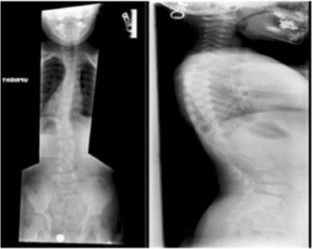

Fig. 4